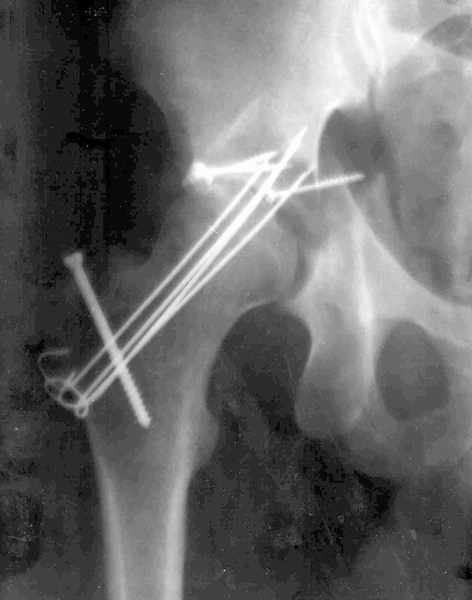

Мужчина 32 года, автотравма 6 недель назад. При поступлении был установлен диагноз "Ацетабулярный перелом". Вывих бедра не был установлен.

После установления вывиха бедра через 3 недели после травмы больному выполнена попытка открытой репозиции, остеосинтез вертлюжной впадины, Бедро фииксировано трансартикулярно спицами. После операции неврит седалищного нерва. В течение ещё 3-х недель после операции установлено что отломки не репонированы, вывих бедра не устранён (см. КТ и рентгенограмму), неврологической динамики нет. Возние вопрос о повторном оперативном вмешательстве по поводу чего разгорелись жаркие споры и сформировалось следующие мнения:1. Тотальное эндопротезирование с цементной фиксацией чашки протезом "ЭСИ" (другого протеза нет)2. Повторная открытая репозиция бедра с замещением дефектов вертлюжной впадины аутокостью с целью подготовки для последующего эндопротезирование. Предполагается фиксация тазобедренного сустава в послеоперационном периоде гипсовой повязкой или аппаратом внешней фиксации.Прошу высказать ваше мнение о тактике дальнейшего лечения пациента, о предложенных вариантах. Отдельный вопрос о возможности первичного тотального эндопротезирования при ацетабулярных переломах. (Лечащий врач настаивал перед первой операцией на выполнении тотального эндопротезирование с цементной фиксацией чашки через 3 недели после травмы)

Было бы существенным посмотреть обзорную R-грамму до операции. По данным послеоперационных снимков и КТ имеется низкий двухколонный перелом или

высокий Т-образный перелом с отрывом свода. Для уточнения необходиы косые проекции (Judet). Весь ли седалищный нерв молчит или только м/б порция?

Xray1

Xray2

Высылаю прямой обзорный и косой подвзошный снимки, косой запирательный неудовлетворительного качества.